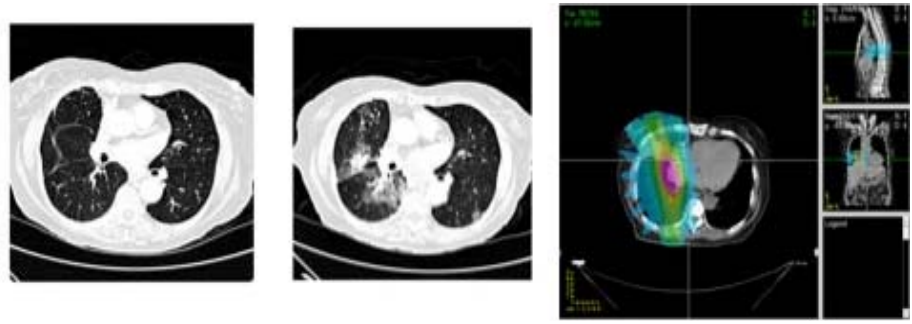

Patients who undergo radiation therapy for lung cancer often are monitored for tumor response through post-therapy CT scans. These images may also demonstrate early signs of normal tissue toxicities induced by the radiation. This project investigates computerized image analysis methods to identify, quantify, and analyze potential image-based signs of lung damage due to radiation therapy. Students will work with advanced image registration algorithms to spatially align the pre- and post-therapy CT scans of radiation therapy patients. Read more

Figure 2: (left) Baseline CT scan from a lung cancer patient undergoing radiation therapy. (center) The same CT section after radiation therapy demonstrating normal lung tissue damage. (right) The radiation dose map from a different patient. The expectation is that regions of increased normal tissue damage correspond with regions of higher radiation dose.